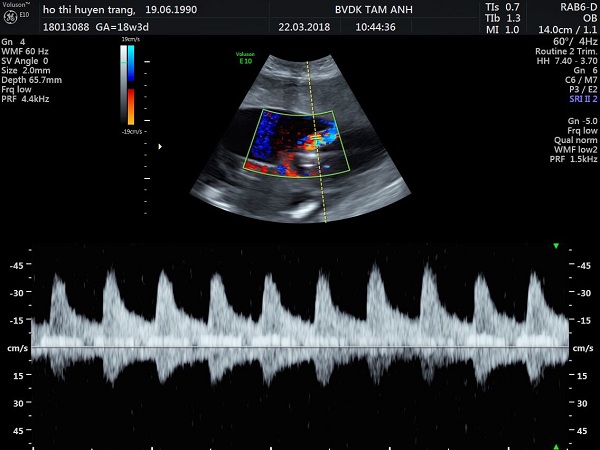

Chị Huyền Trang khám lần đầu tại bệnh viện ngày 14/3, lúc thai được 17 tuần 2 ngày. Bệnh nhân mang song thai hai buồng ối, một bánh nhau, nhau bám mặt trước, gặp Hội chứng truyền máu song thai giai đoạn II-III. Góc ối sâu nhất của “thai cho” là 8mm, góc ối sâu nhất của “thai nhận” là 80mm. Với sự phức tạp của ca bệnh, thai phụ được thạc sĩ, bác sĩ Đinh Thị Hiền Lê tư vấn nên đi nước ngoài để thực hiện ca phẫu thuật, nếu không hai thai nhi sẽ gặp nguy hiểm, thậm chí tính mạng của người mẹ cũng bị đe doạ.

Trong khi gia đình chưa thể ra nước ngoài để thực hiện phẫu thuật thì tình trạng 3 mẹ con tiến triển nhanh theo chiều hướng xấu đi. Một tuần sau, thai phụ quay trở lại thăm khám. Lúc này tình trạng của 2 thai nhi đã rất nguy kịch. Góc ối sâu nhất của “thai cho” là 5mm, không nhìn thấy bàng quang, Doppler cuối tâm trương = 0. Với “thai nhận”, hình ảnh trục tim lệch sang bên trái, 4 buồng tim bất tương xứng, tâm nhĩ phải giãn to, hở van ba lá, hẹp động mạch phổi. Hai thận tăng âm, góc ối sâu nhất của thai nhận là 99 mm. Tiên lượng rất xấu.

Sau khi mổ nội soi một ngày, sản phụ được siêu âm kiểm tra cho thấy các dấu hiệu đều tốt ở mức ngoài mong đợi, chỉ chậm trễ một ngày sẽ ảnh hưởng đến tính mạng của 2 em bé.